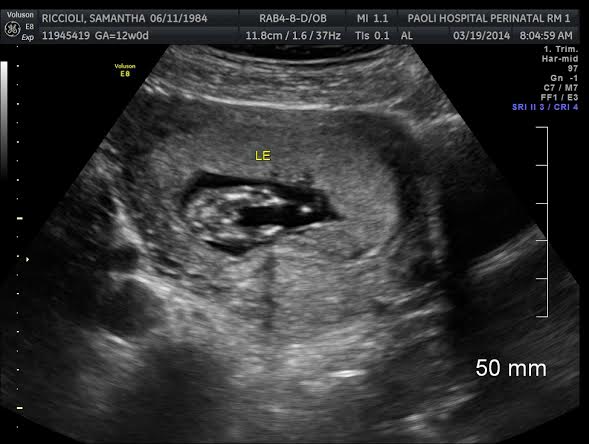

i think its a GIRL. Look at my potty shot at 12 weeks. VERY boyish looking.Attachment 18038